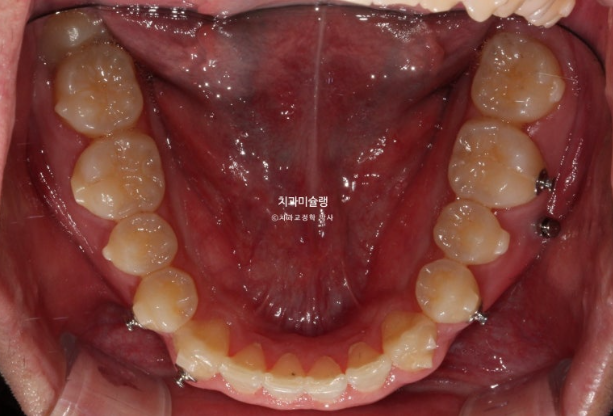

2022년 10월부터 24년 4월까지 1년반동안 첫세트 장치를 모두 낀 후 모습입니다.

24.04

가위교합은 해결이 되었지만 아직 어금니 교합이 긴밀하지 않습니다.

배열은 완벽합니다.

중심선 등을 좀 더 바로잡고자 재제작에 들어갑니다.

재제작 장치는 17개가 나왔고 24년 5월부터 24년 11월까지 꼈습니다.